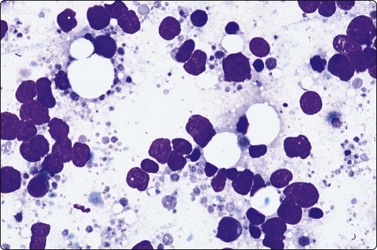

image

Fig. 5.8 Infectious mononucleosis

Many transforming lymphocytes, plasmacytoid cells and immunoblasts (MGG, HP).